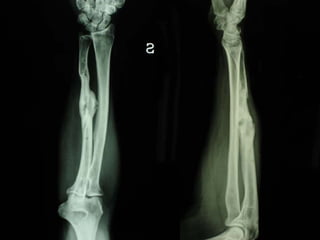

Dal Gennaio 2000 al Febbraio 2006 abbiamo trattato 167 fratture chiuse  con placca percutanea  in 164 pazienti :  27 lesioni diafisarie di gamba, 12 piloni tibiali ,  11 fratture prossimali di tibia, 36 fratture sovracondiloidee di femore, 17 fratture diafisarie di femore, 43 fratture metaepifisarie prossimali di omero, 21 diafisarie d’omero.  156 guarigioni 8 fallimenti

Dal Giugno 2002 al Dicembre 2004 abbiamo trattato 5 fratture esposte: 3 di tibia e 2 di ulna 5 guarigioni

I buoni risultati ottenuti dipendono da 5 punti fondamentali:   una accurata riduzione percutanea della frattura  precise vie di accesso  l’utilizzo della placca che consenta il più lungo braccio di leva possibile il pretensionamento della placca  una sintesi con un ridotto numero di viti